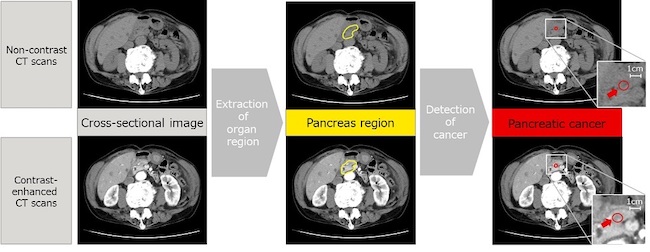

The precise and early detection of signs of pancreatic cancer in non-contrast CT scans represents a difficult task due to the low contrast of images and the unclear boundaries between the pancreas and other organs. To address this issue, Fujitsu and Southern Tohoku General Hospital aim to develop an AI technology that can identify the region corresponding to the pancreas (part marked yellow in figure 1) and detect the suspected parts affected by cancer (part marked red in figure 1). The technology achieves this by estimating the continuity between the anterior and posterior cross-sectional images in consideration of the anatomical tissue connection and automatically performs three-dimensional analysis including the anterior and posterior cross-sectional images in areas with strong continuity and planar analysis in areas with weak continuity.